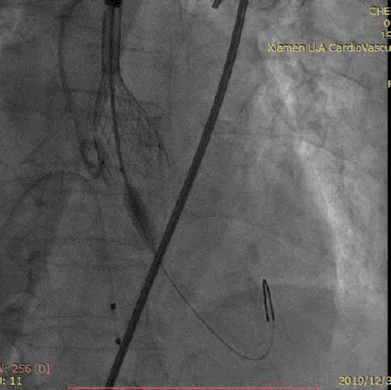

释放VenusA-Valve L26瓣膜